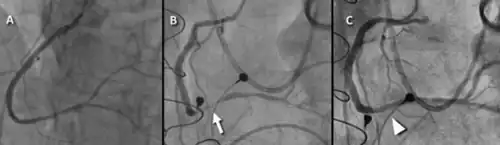

| a) Preoperative angiogram b) postoperative angiogram with focal spasm at the arrow c) resolution after intracoronary nitroglycerin | |